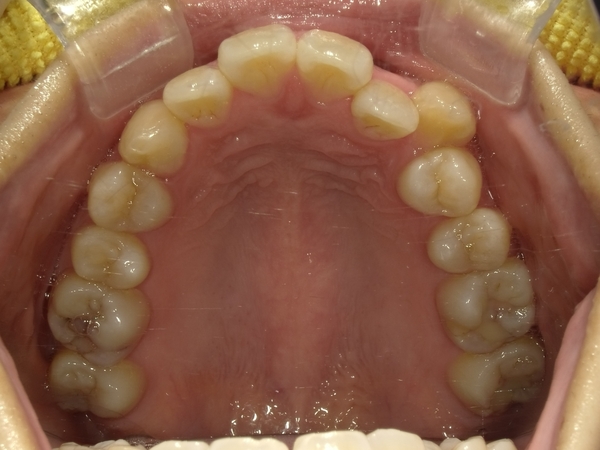

ガタガタとした歯並びや八重歯(叢生)CASE68